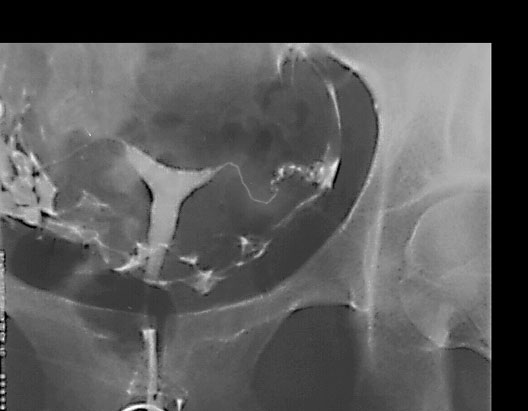

Hysterosalpingogram

1. Right Uterine Tube

2. Uterus

3. Left Uterine Tube

4. Ovary